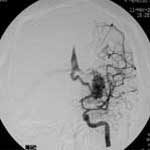

二、脑动静脉畸形(AVM)

---- Spetzler对AVM的分级方法已越来越多地被人们接纳和采用。脑AVM最危险的症状之一是出血。AVM每年的出血率为3%~4%,第一年内再出血约6%。每次出血的致残率为30%,病死率为12.5%,而积极治疗的总残废率加病死率在10%以下。

血管内栓塞对于单支或少数供血动脉的AVM,特别是新近出血的病例,可以达到微侵袭、痛苦小、疗效迅速的目的。

近来改变栓塞方式,将导管直接放置 畸形血管团内,注射NBCA胶,可使畸形团的解剖 治愈率提高至27%。再加上更细、超滑的微导管问世,栓塞的并发症更为降低。针对大型、功能区 的AVM栓 塞可缩小其体积,改善血液动力学分布,以利于显微外科技术切除或放射外科治疗,是后二者的重要辅助手段。